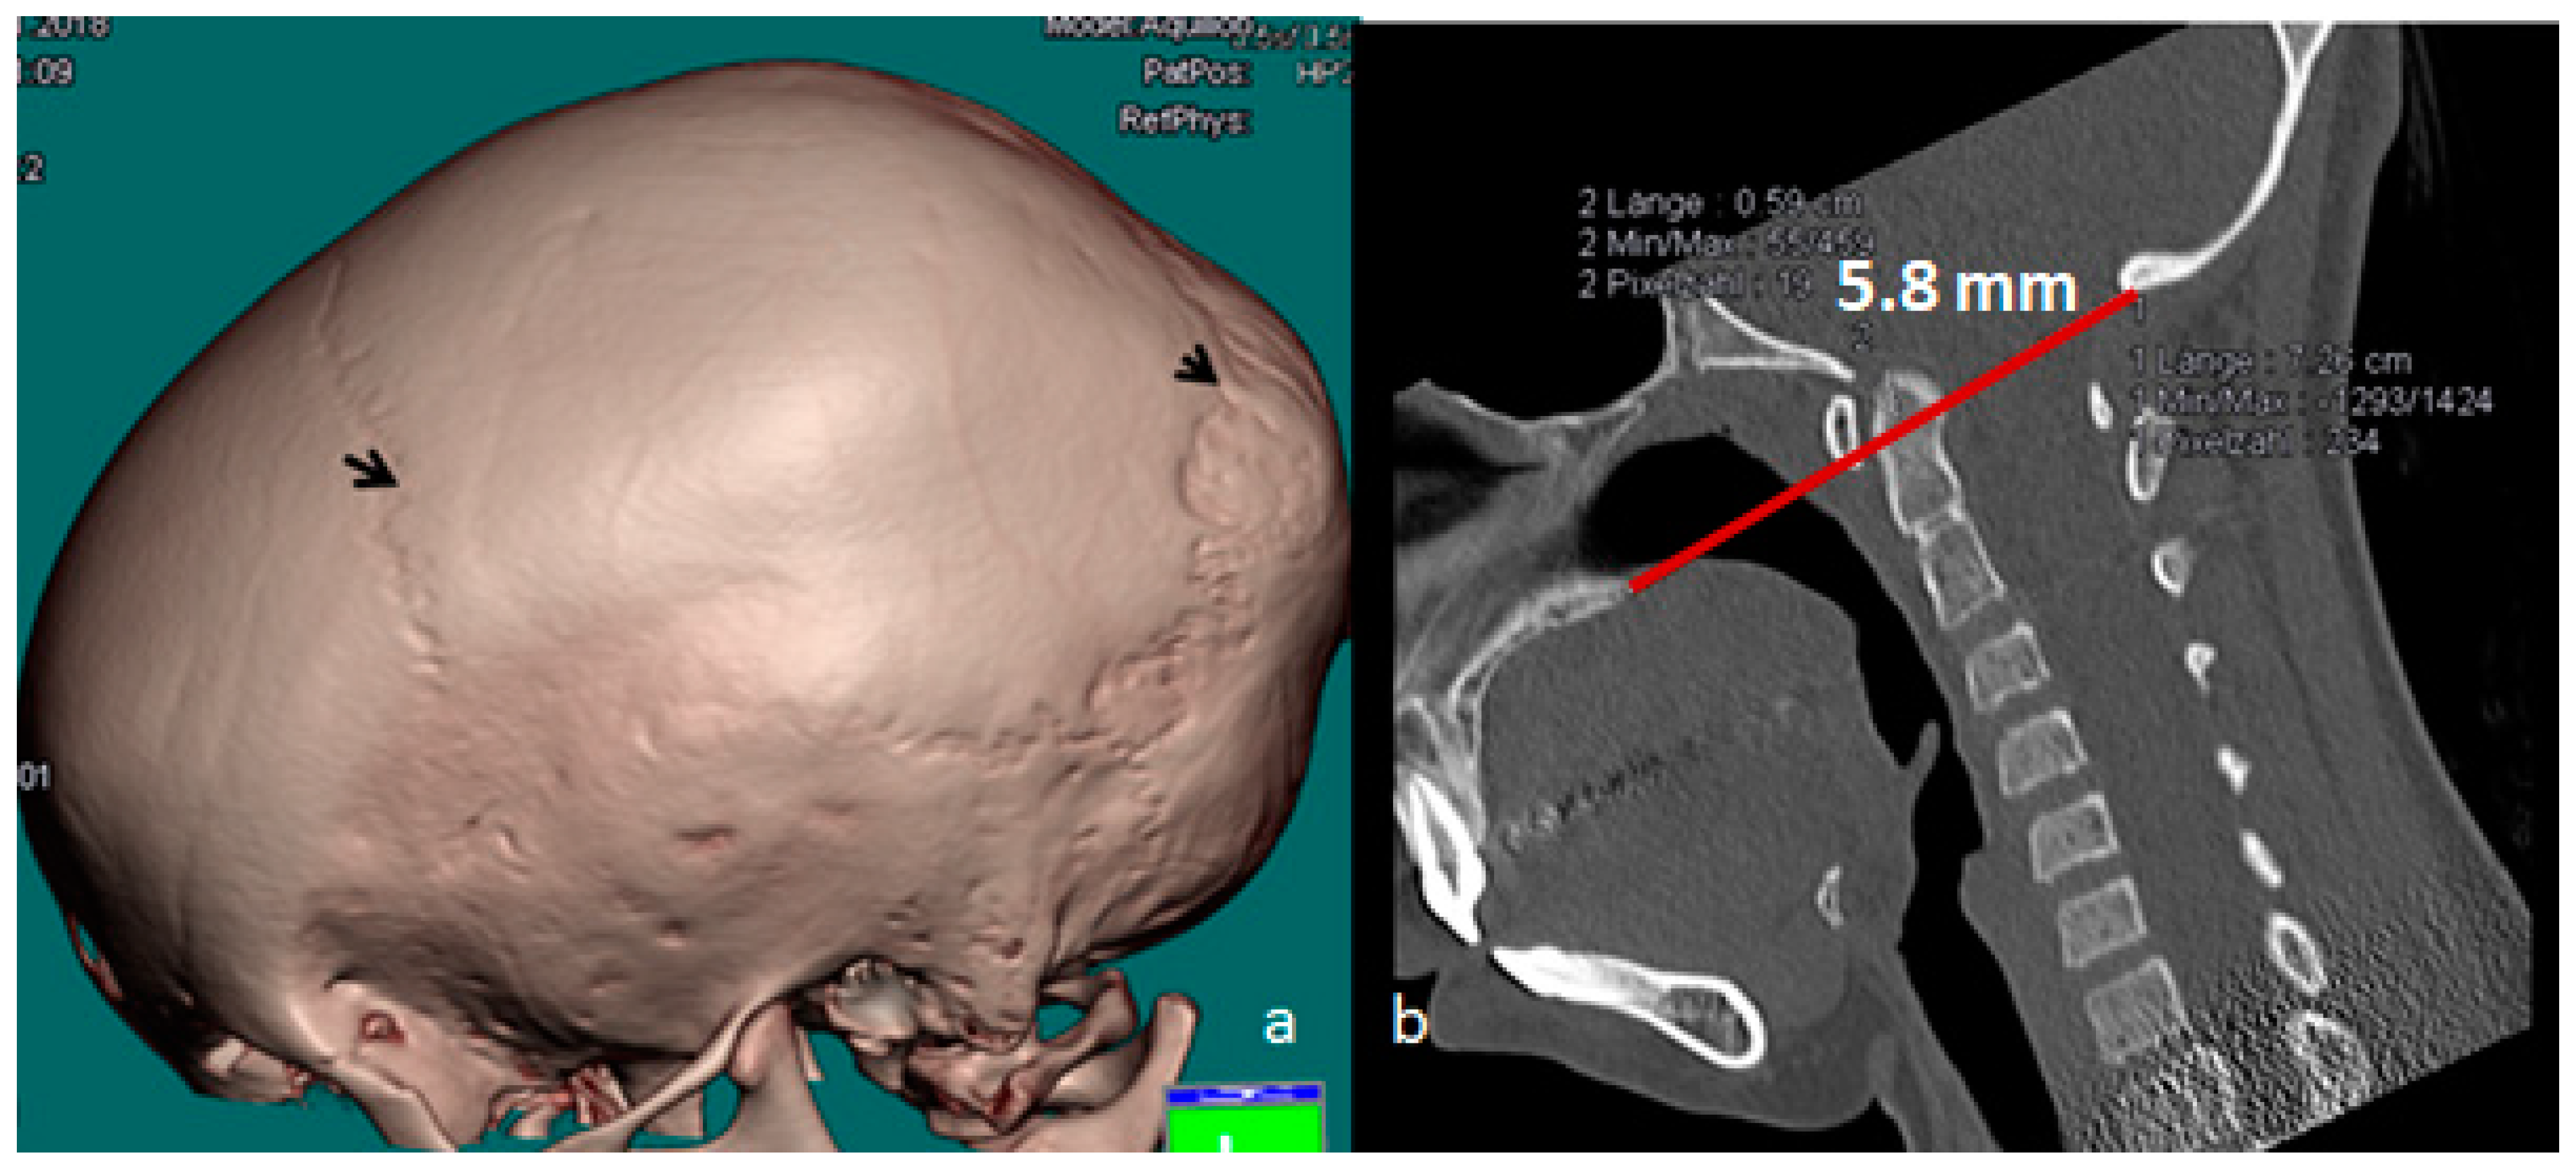

3.1. Patients with Osteogenesis Imperfecta Type I

Patients with Osteogenesis Imperfecta Type IVB